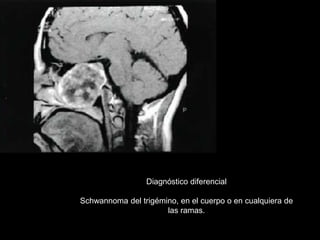

Diagnóstico diferencial

Schwannoma del trigémino, en el cuerpo o en cualquiera de

las ramas.